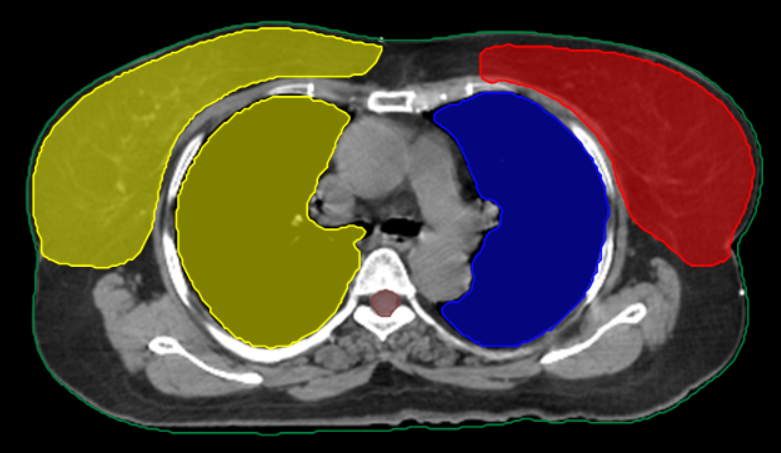

LT Breast Challenge

3D-CRT